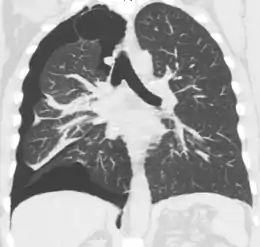

Computed tomography

A CT scan is not necessary for the diagnosis of pneumothorax, but it can be useful in particular situations. In some lung diseases, especially emphysema, it is possible for abnormal lung areas such as bullae (large air-filled sacs) to have the same appearance as a pneumothorax on chest X-ray, and it may not be safe to apply any treatment before the distinction is made and before the exact location and size of the pneumothorax is determined.[15] In trauma, where it may not be possible to perform an upright film, chest radiography may miss up to a third of pneumothoraces, while CT remains very sensitive.[18]

A further use of CT is in the identification of underlying lung lesions. In presumed primary pneumothorax, it may help to identify blebs or cystic lesions (in anticipation of treatment, see below), and in secondary pneumothorax, it can help to identify most of the causes listed above.[15][19]